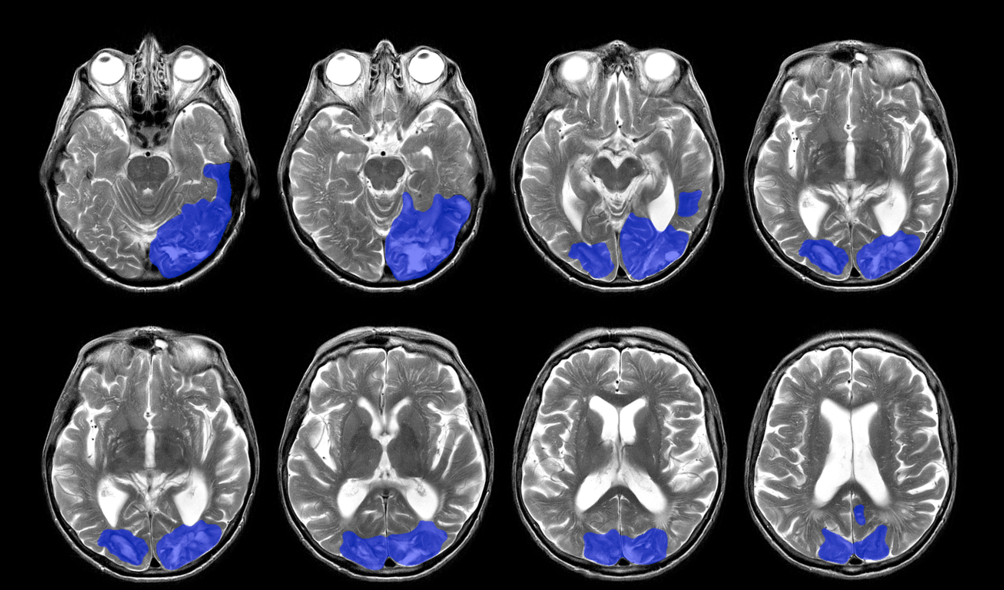

At the University of Oxford, I developed a new screening test for visual perception difficulties after stroke, the Oxford Visual Perception Screen or OxVPS.

Visual perception refer to how the brain interprets the information coming from the eyes. Our eyes might be working fine, but after brain injury our brain might not be able to recognise objects or faces anymore, make up words from letters, or direct visual attention. Vision and visual perception problems are common after stroke but are not always picked up in a busy clinical environment. The available tests are too long and some are not suitable for stroke survivors with speech difficulties.

With my research, I want to improve diagnosis of visual perception difficulties after stroke. I have interviewed occupational therapists and orthoptists (or eye movement specialists) about how they screen for visual perceptual difficulties and what their clinical needs are. They told me that they want something that is quick and does not require much training. In a national survey, I asked their colleagues from all over the UK if they agreed. With all that input, I then developed a prototype of a visual perception screen. I made both a paper version and an app. The screen has tests for object recognition, face perception, reading, visuo-motor skills, and more. We have asked opinions of stroke survivors and older volunteers too. They told us how to make the instructions more clear and how to make the app user-friendly.

At Durham University, we further finetuned the OxVPS and collected normative data of over 100 health volunteers to establish the normal range of scores on OxVPS. We have also evaluated the diagnostic accuracy of OxVPS. With support of the NIHR, we asked over stroke survivors around Durham and Oxford to complete OxVPS and a gold standard test of visual perception that takes much longer to complete. We compared stroke survivor’s results on both tests to see if the new quick screening test, OxVPS, gives similar results as the gold standard test. We will also be working on providing clinicians with rehabilitation advice for all the conditions that OxVPS screens for. For this, we will summarise the literature on visual perception rehabilitation and discuss best practice recommendations with a panel of experts.